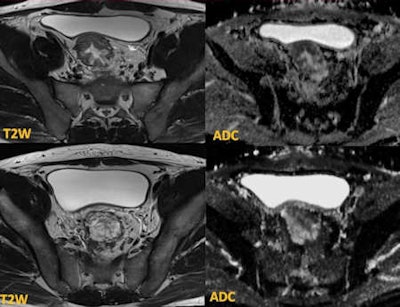

Differentiating the tumor from the rectal wall often is difficult on fast spin-echo (FSE) T2-weighted (T2W) imaging, he continued. In particular, a small, low rectal tumor can be challenging because of the contrast difference between the tumor and adjacent intrinsic and extrinsic sphincter complex. In such circumstances, DWI with high B-values plays a major role in identifying the tumor. Coregistering high-resolution T2W images with the DWI and apparent diffusion coefficient (ADC) map significantly increases the sensitivity of identifying the tumor.

High-resolution T2W imaging demonstrates detailed anatomy of the rectal wall, but due to low contrast between the tumor and the rectal wall, accurate staging can be difficult, he confirmed. On the B-value images, although the signal-to-noise ratio is low, the contrast between the high signal tumor and the rectal wall can be clearly demonstrated. Moreover, when the DWI is coregistered with T2W images, the T-staging can be performed with high accuracy.

Patients with rectal cancer may have coexisting cancer of other pelvic organs such as the prostate and bladder. DWI can identify these tumors. Early detection of coexisting tumors is vital to ensure the best outcome for these patients because surgical and radiotherapy planning in these cases can be quite complex and often requires a multidisciplinary approach.